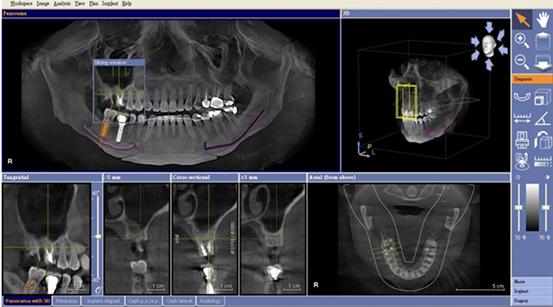

CT對於植牙手術,最大的便利性之一,即是具有模擬各家廠牌植體的功能,讓牙醫師在術前判斷植體埋入的位置是否恰當。由於CT所拍攝出來的影像是立體的,可以360度旋轉,進一步判斷植體的寬度,避免因為患者的顎骨結構的不同,穿到顎骨的外側,或是壓迫到神經。

CT能做植體與牙齒的360度檢查,並模擬植體,安效提高手術安全性

電腦模擬植牙示意圖